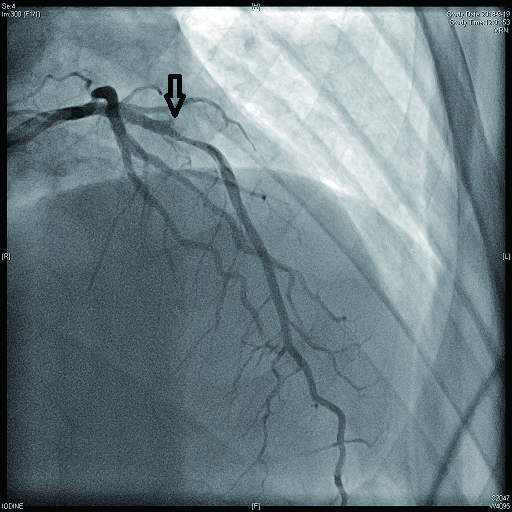

2 结果 本研究收集7例De winter综合征患者,6例进行了急诊冠脉造影,胸痛至球囊扩张平均时间为3.3 h,1例进行择期冠脉造影。其中,3例为前降支近段严重病变,1例为第一对角支闭塞,3例为前降支中段闭塞,2例合并多支血管病变,5例为单支血管病变,均行前降支支架植入术(表 4)。1周内行心脏彩超检查,4例出现室壁运动减弱,2例EF值小于50%,2例心脏形态结构未见异常,1例患者术后第2天因个人原因自动出院,未完善心脏彩超(表 5)。观察7例患者住院期间心电图演变情况,其中有3例在PCI术后出现前壁导联ST段抬高,4例未出现ST段抬高(表 5)。病例1住院期间出现室性心动过速,病例7患在急诊科就诊时发生呼吸心搏骤停,经抢救后送导管室行急诊冠脉造影。另外,所有患者经药物及介入治疗后,均症状缓解出院,院外长期服用阿司匹林100 mg/d+替格瑞洛90 mg/12 h+阿托伐他汀40 mg/瑞舒伐他汀20 mg等药物,出院1个月后电话随访,7例患者均无胸痛、气促发作及再住院,无死亡病例。

表 4 7例患者冠脉造影及介入治疗情况

| 病例2 |

是 |

3(图 6~8) |

LAD近段 |

次全闭塞 |

2级 |

LAD近段植入支架1枚 |

| 注:LAD为左冠状动脉前降支; TIMI为心肌梗死溶栓治疗 |

表 5 7例患者的心电图演变及心脏彩超结果

| 病例2 |

否 |

左室前间壁中下段运动稍减弱,EF 59% |